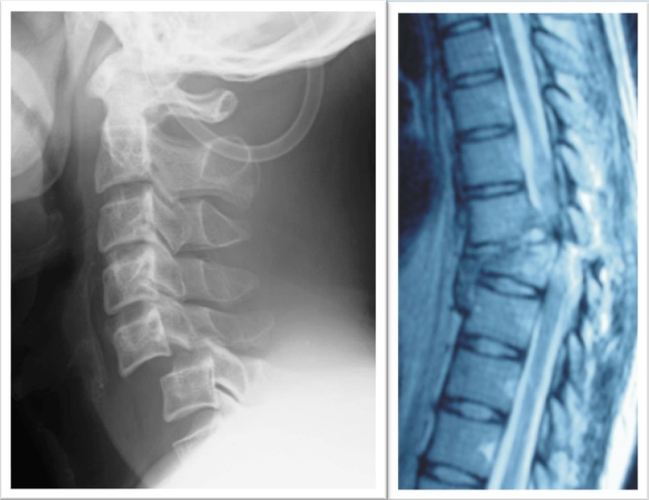

「iPS細胞を用いた脊髄損傷の再生医療」

脊髄損傷の再生医療